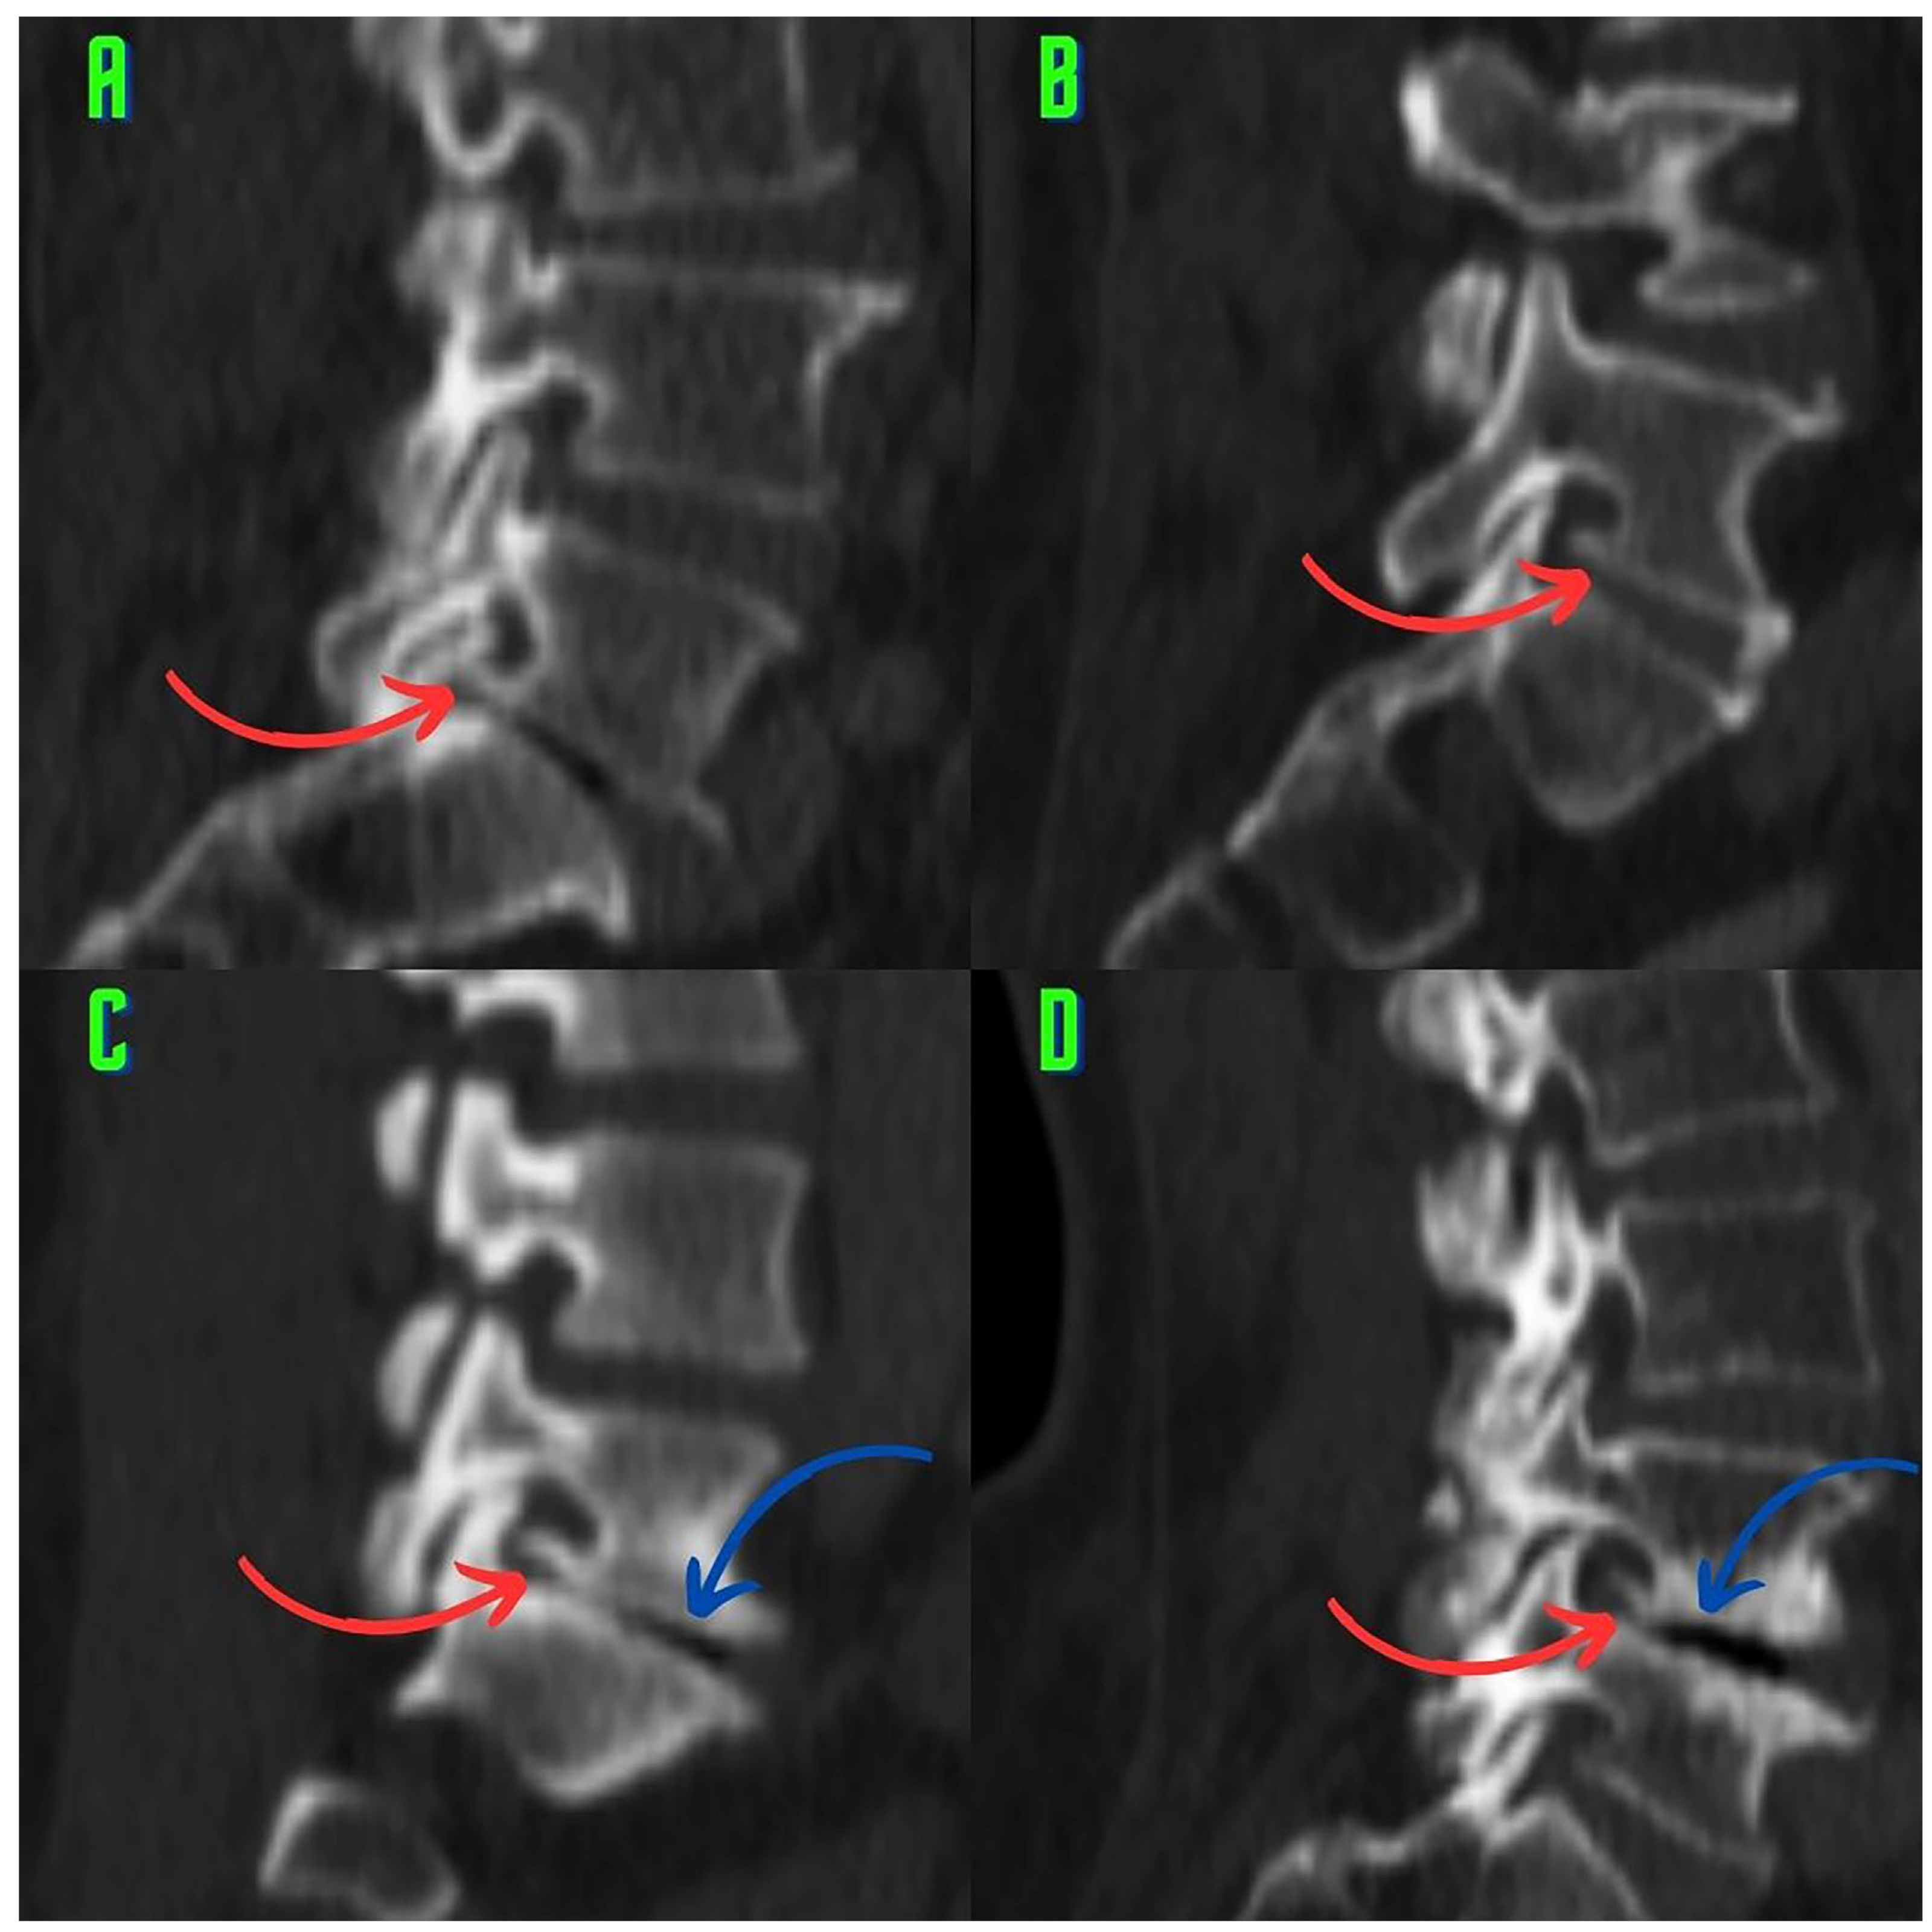

2.3. Image Analysis and Research Methods

3. Results

4. Discussion